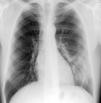

The patient denied smoking, alcoholic or drug habits and there was no history of previous admissions. Clinical evaluation of the patient revealed only discrete bronchospasm after pulmonary auscultation. A chest X-ray showed unilateral inferior rib notching of the 4–7th left ribs, inferior left lung hypotransparency and prominent vasculature (Figs. 1 and 2).

DiscussionClinical manifestations of the systemic-pulmonary arterial fistulae may be misinterpreted as patency of the ductus arterious or arterio-venous malformations and the symptoms depend, in part, on the functional repercussion that is proportional to the vessel size involved in the abnormal vascular anastomosis and heart distance.2,8 Chest X-ray in this type of vascular malformations demonstrates unilateral inferior rib notching and lung hypotransparency, suggesting pulmonary infiltrates and/or increased blood vessels (as in our case report).3